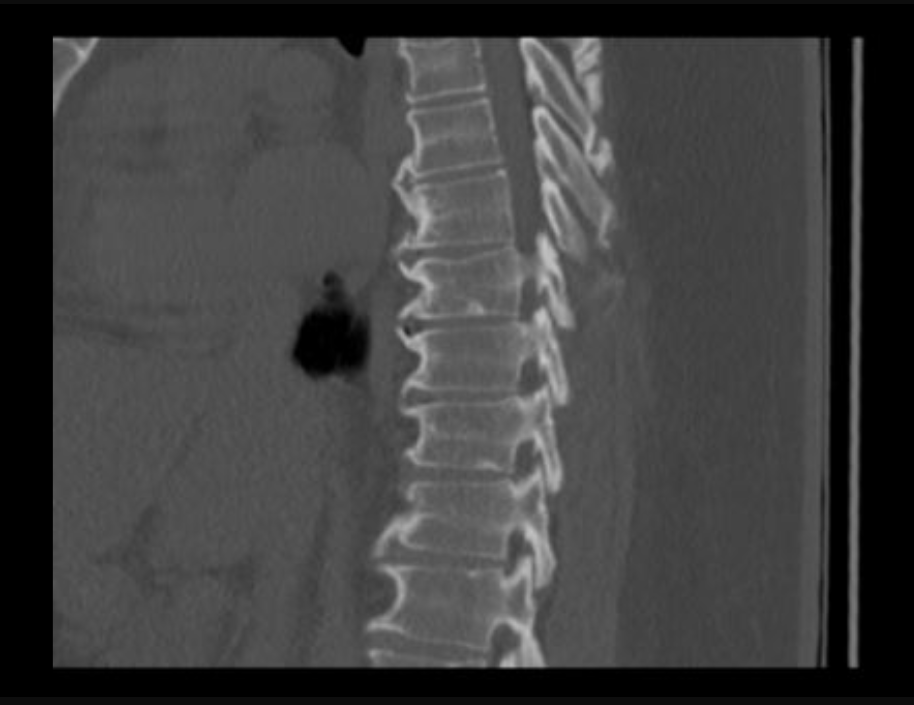

I’ve been diagnosed with Diffuse Idiopathic Skeletal Hyperostosis (DISH) and degenerative disc disease — both cause my spinal bones to stiffen and press on nerves. The pain runs across my lower back, hips, and legs, and sometimes even causes numbness around my lower back and thighs. I’ve tried to keep pushing through, but lately, even sleeping or sitting too long hurts.